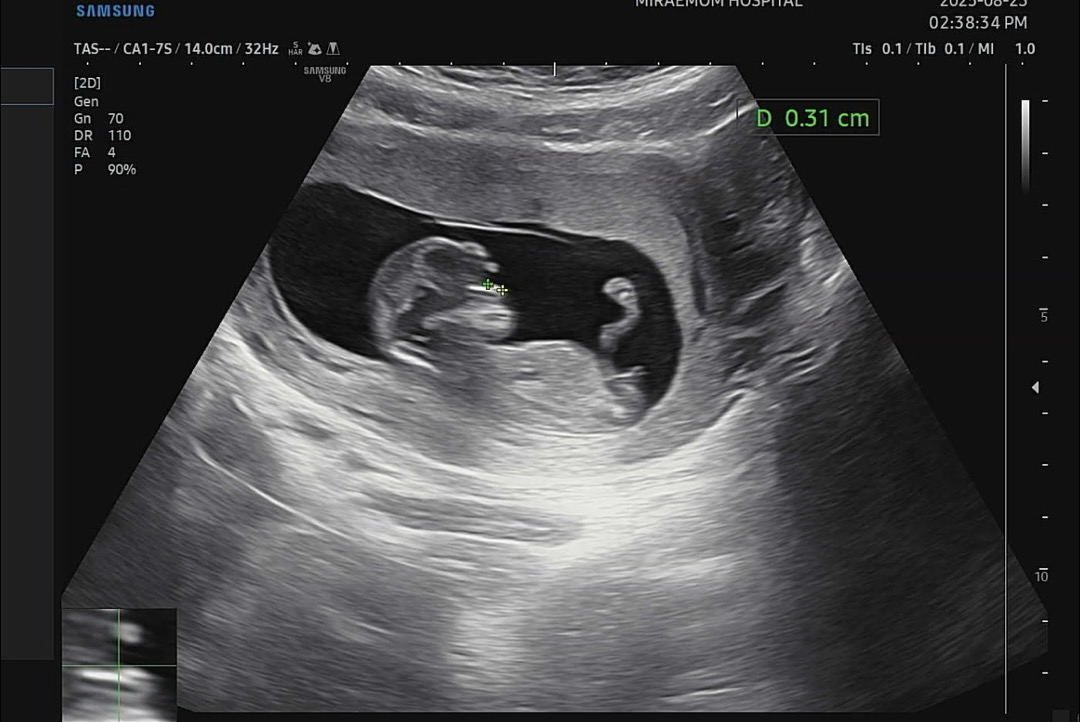

각도법 참견 부탁드립니다 ㅠㅠ 🌙

오늘 1차기형아 검사하고 왔습니다 ! 늘 보던 선생님이 아니라 그냥 아무말 없이 진료만 봐주셔서 … 너무 궁금하네요 ㅠ ㅠ